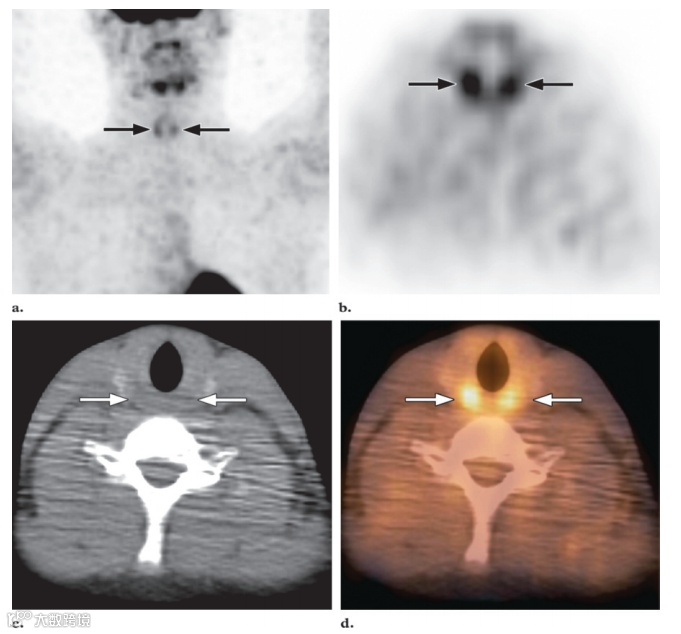

图4. MIP FDG PET 图像 (a) 和横向FDG PET (b)、CT (c) 和融合PET/CT (d) 图像显示杓状肌的摄取略有增加 (箭头) 。

喉部和声带通常没有摄取或轻度对称摄取,可能呈倒U形(图4)。重要的是指导儿童在摄取阶段不要说话,因为过多的说话可能会导致喉部结构出现明显的活动。声带摄取不对称提示恶性肿瘤、治疗后改变或单侧声带麻痹等疾病的可能性。有时可以注意到可变的FDG摄取,这与口底的颏舌肌相对应,当患者仰卧时,颏舌肌会使舌头向前。肌肉活动也可以在眼外肌的汇合处以及这些肌肉的长度上识别出来(图5)。偶尔,临床上甲状腺功能正常的患者会出现偶然的弥漫对称性摄取。根据我们的经验,这种情况在儿童中相对罕见。然而,这种弥漫性甲状腺摄取可能代表Graves病或甲状腺炎。甲状腺良性结节或恶性肿瘤中可见局部甲状腺摄取,在这种情况下需要进一步检查。